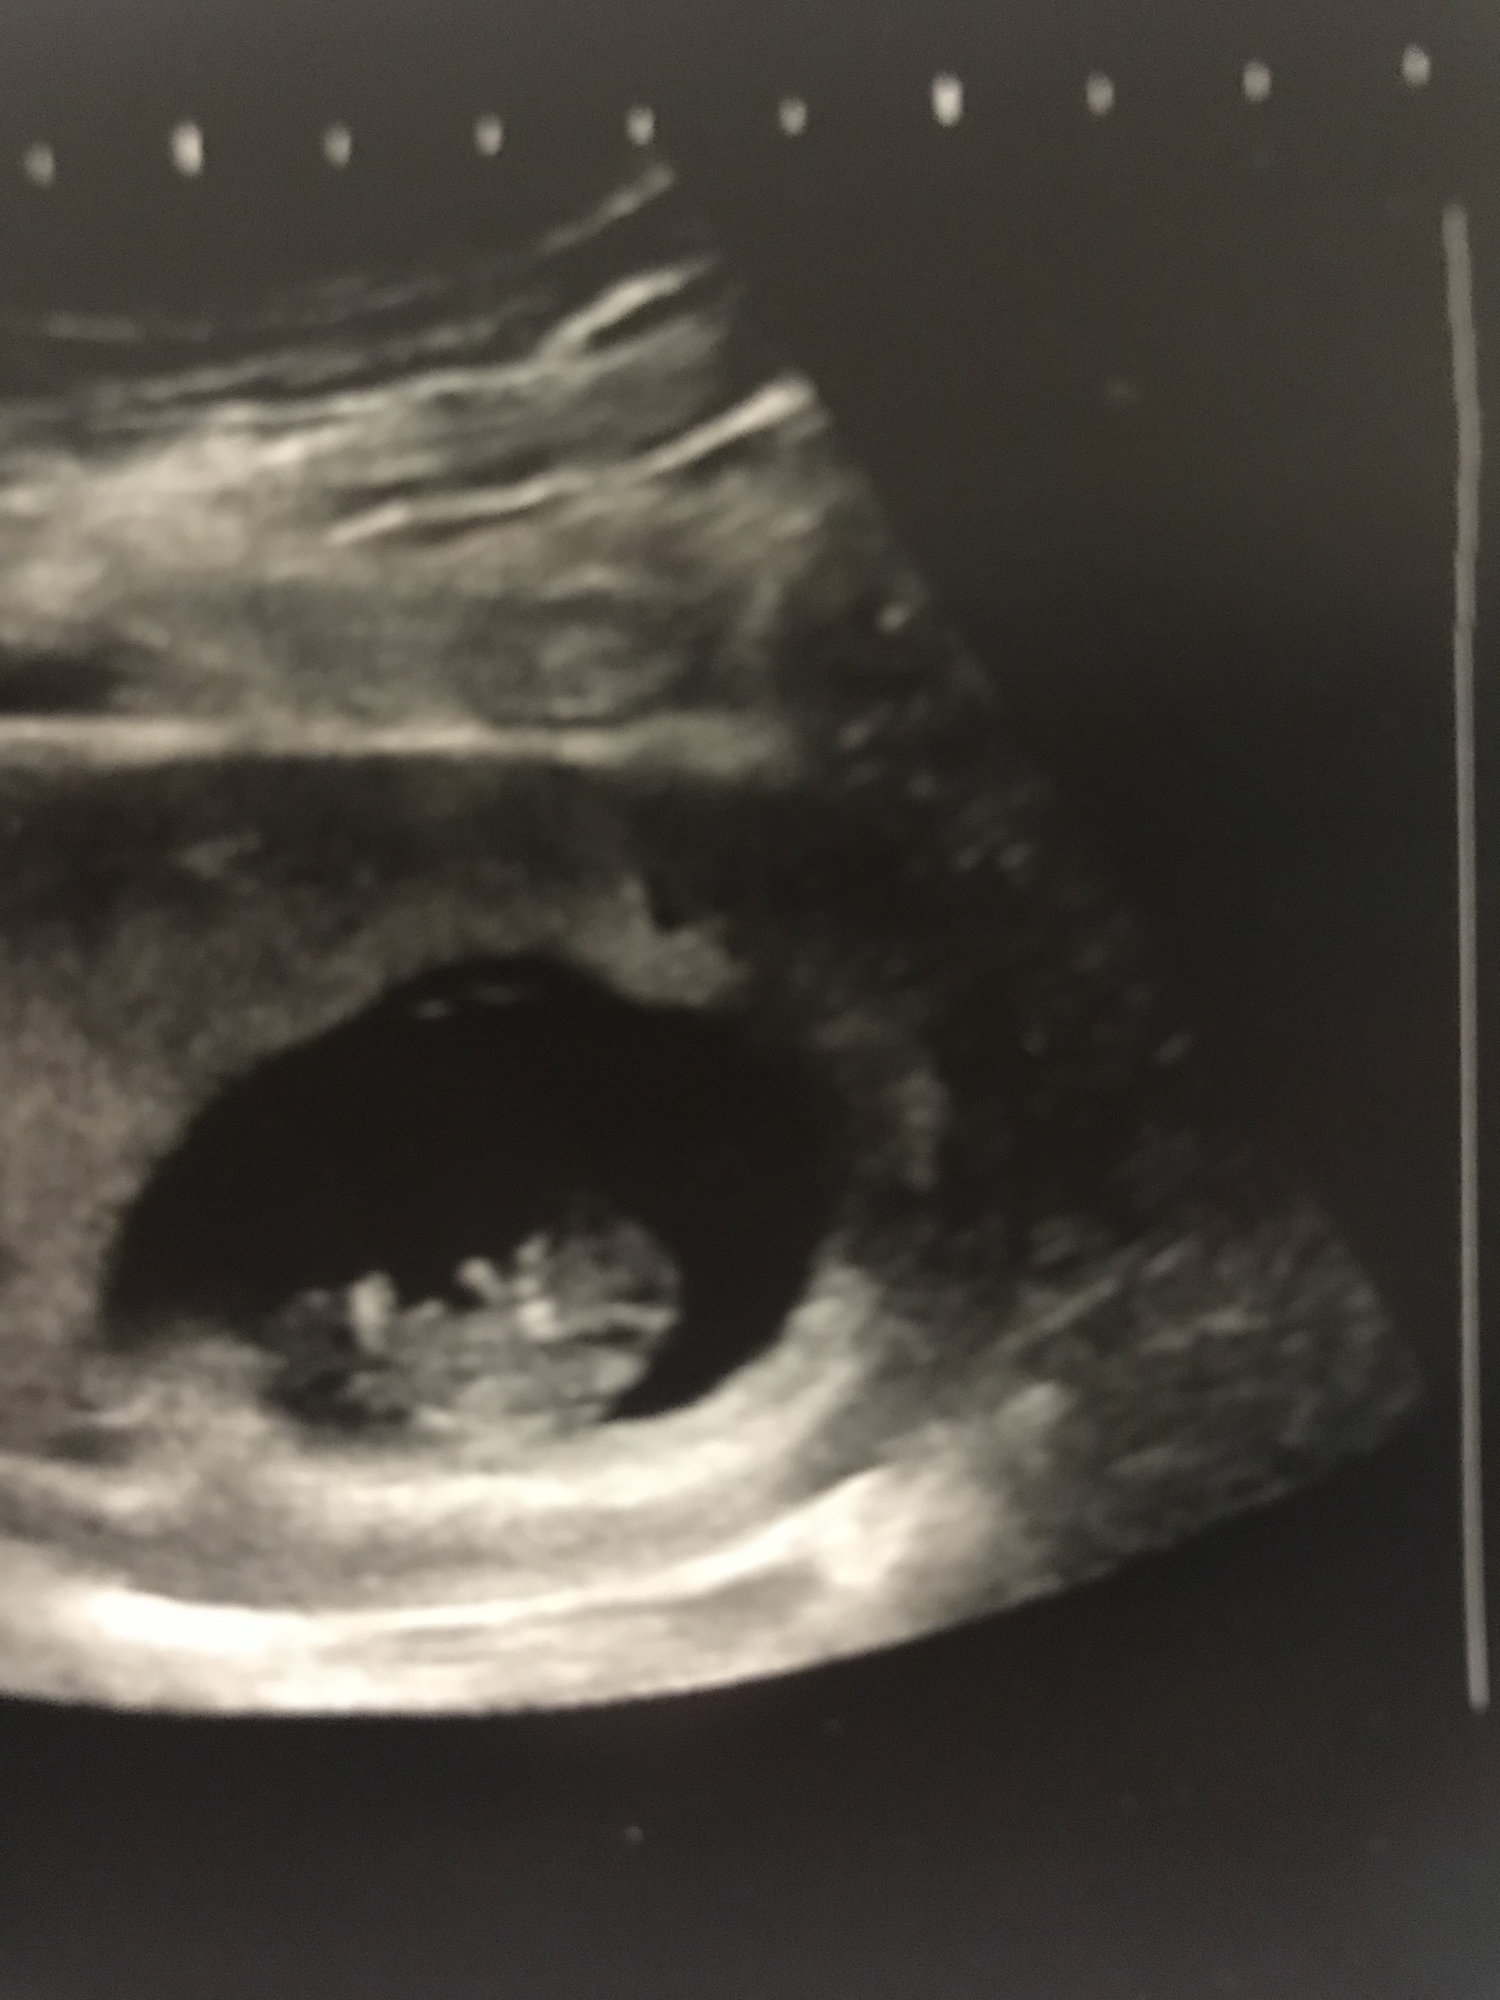

Ultrasound pic from this morning. Yolk sac and head are on the left and feet towards the right side of the picture. 9 weeks 1 day with a heartbeat of 171. This baby seemed chill compared to my last one who was flipping around like a little maniac during the first ultrasound.